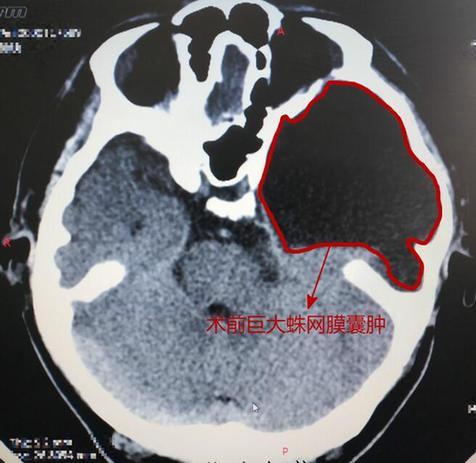

24歲的小楊前一陣開車時不小心造成頭部外傷,當時只有耳朵上方皮膚稍有挫傷,其余一切正常,因此沒有引起重視。2天后,小楊開始出現(xiàn)頭部不適,語言不清,頭部晃動,右側(cè)肢體抖動,持續(xù)大約1分鐘,5分鐘后恢復(fù)意識,就那一天就發(fā)作了3次。小楊趕緊到醫(yī)院行頭顱CT檢查,發(fā)現(xiàn)原來左額顳頂那個位置早就存在一個巨大的蛛網(wǎng)膜囊腫,對腦組織形成明顯壓迫,而這一次腦外傷出血加速了壓迫,造成中線向右移位,保守治療后癥狀有好轉(zhuǎn)。2月9日,腦外傷一周后,小楊再次發(fā)作,比前幾次都要嚴重,口角抽動、不能說話、口角歪斜,急診來到我院。

術(shù)前診斷小楊為蛛網(wǎng)膜囊腫,腦外傷引發(fā)癥狀性癲癇,由于腦組織受壓嚴重,2月11日,孫玉明主任為小楊實施了左側(cè)顳部切口鉆孔穿刺外引流術(shù),燒灼硬膜后,可見少許淡黃色液體流出,順利放入導(dǎo)流管。術(shù)后第一天,引出淡黃色清涼液體150ml,小楊恢復(fù)良好,可以簡單叫“媽媽”。術(shù)后待患者血糖等指標控制達標后,再行囊腫切除手術(shù),徹底解決病灶。